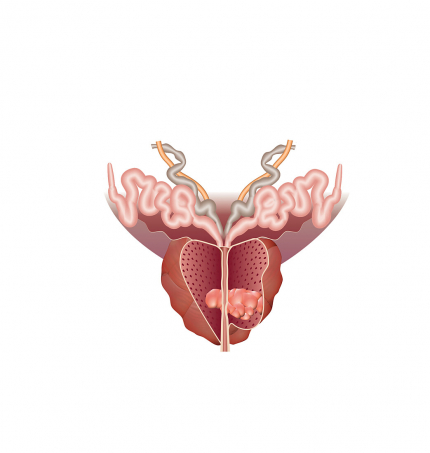

Le cancer de la prostate

La prostate est une glande de l’appareil génital masculin, qui joue un rôle dans la production du sperme.

En 2019, Jiang et al. ont décrit un modèle simple de prostate sur puce qui reproduisait l'interface stroma-épithélial [49]. Ce dispositif (Figure 4) est constitué de deux canaux superposés en PDMS (pour polydiméthylsiloxane) séparés par une membrane microporeuse en polyester, ce qui a permis une communication paracrine1 entre les cellules cancéreuses et les cellules du stroma tout en empêchant un contact direct entre les deux types de cellules afin d'étudier les voies de signalisation biochimique dans l'interface stroma-épithélial2. La communication biochimique entre les cellules épithéliales, stromales et cancéreuses est un facteur clé de la physiopathologie du cancer de la prostate.